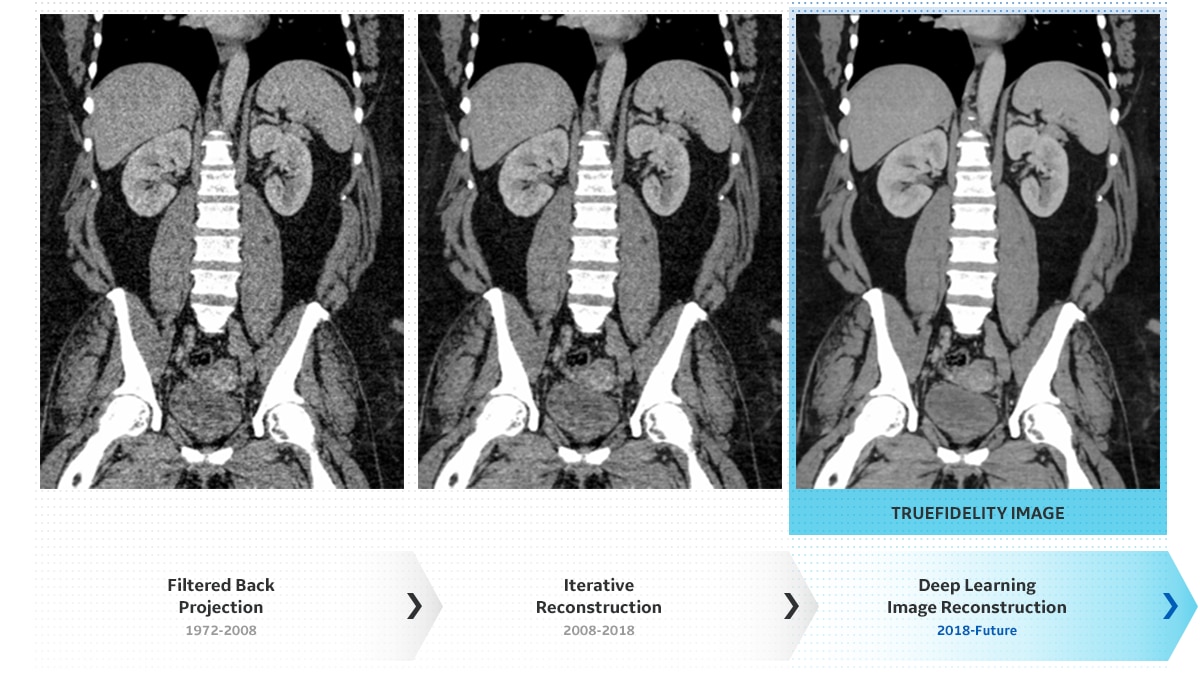

Image Gallery : Reconstruction Technology Comparison

FBP

ASiR-V 50%

Deep Learning Image Reconstruction